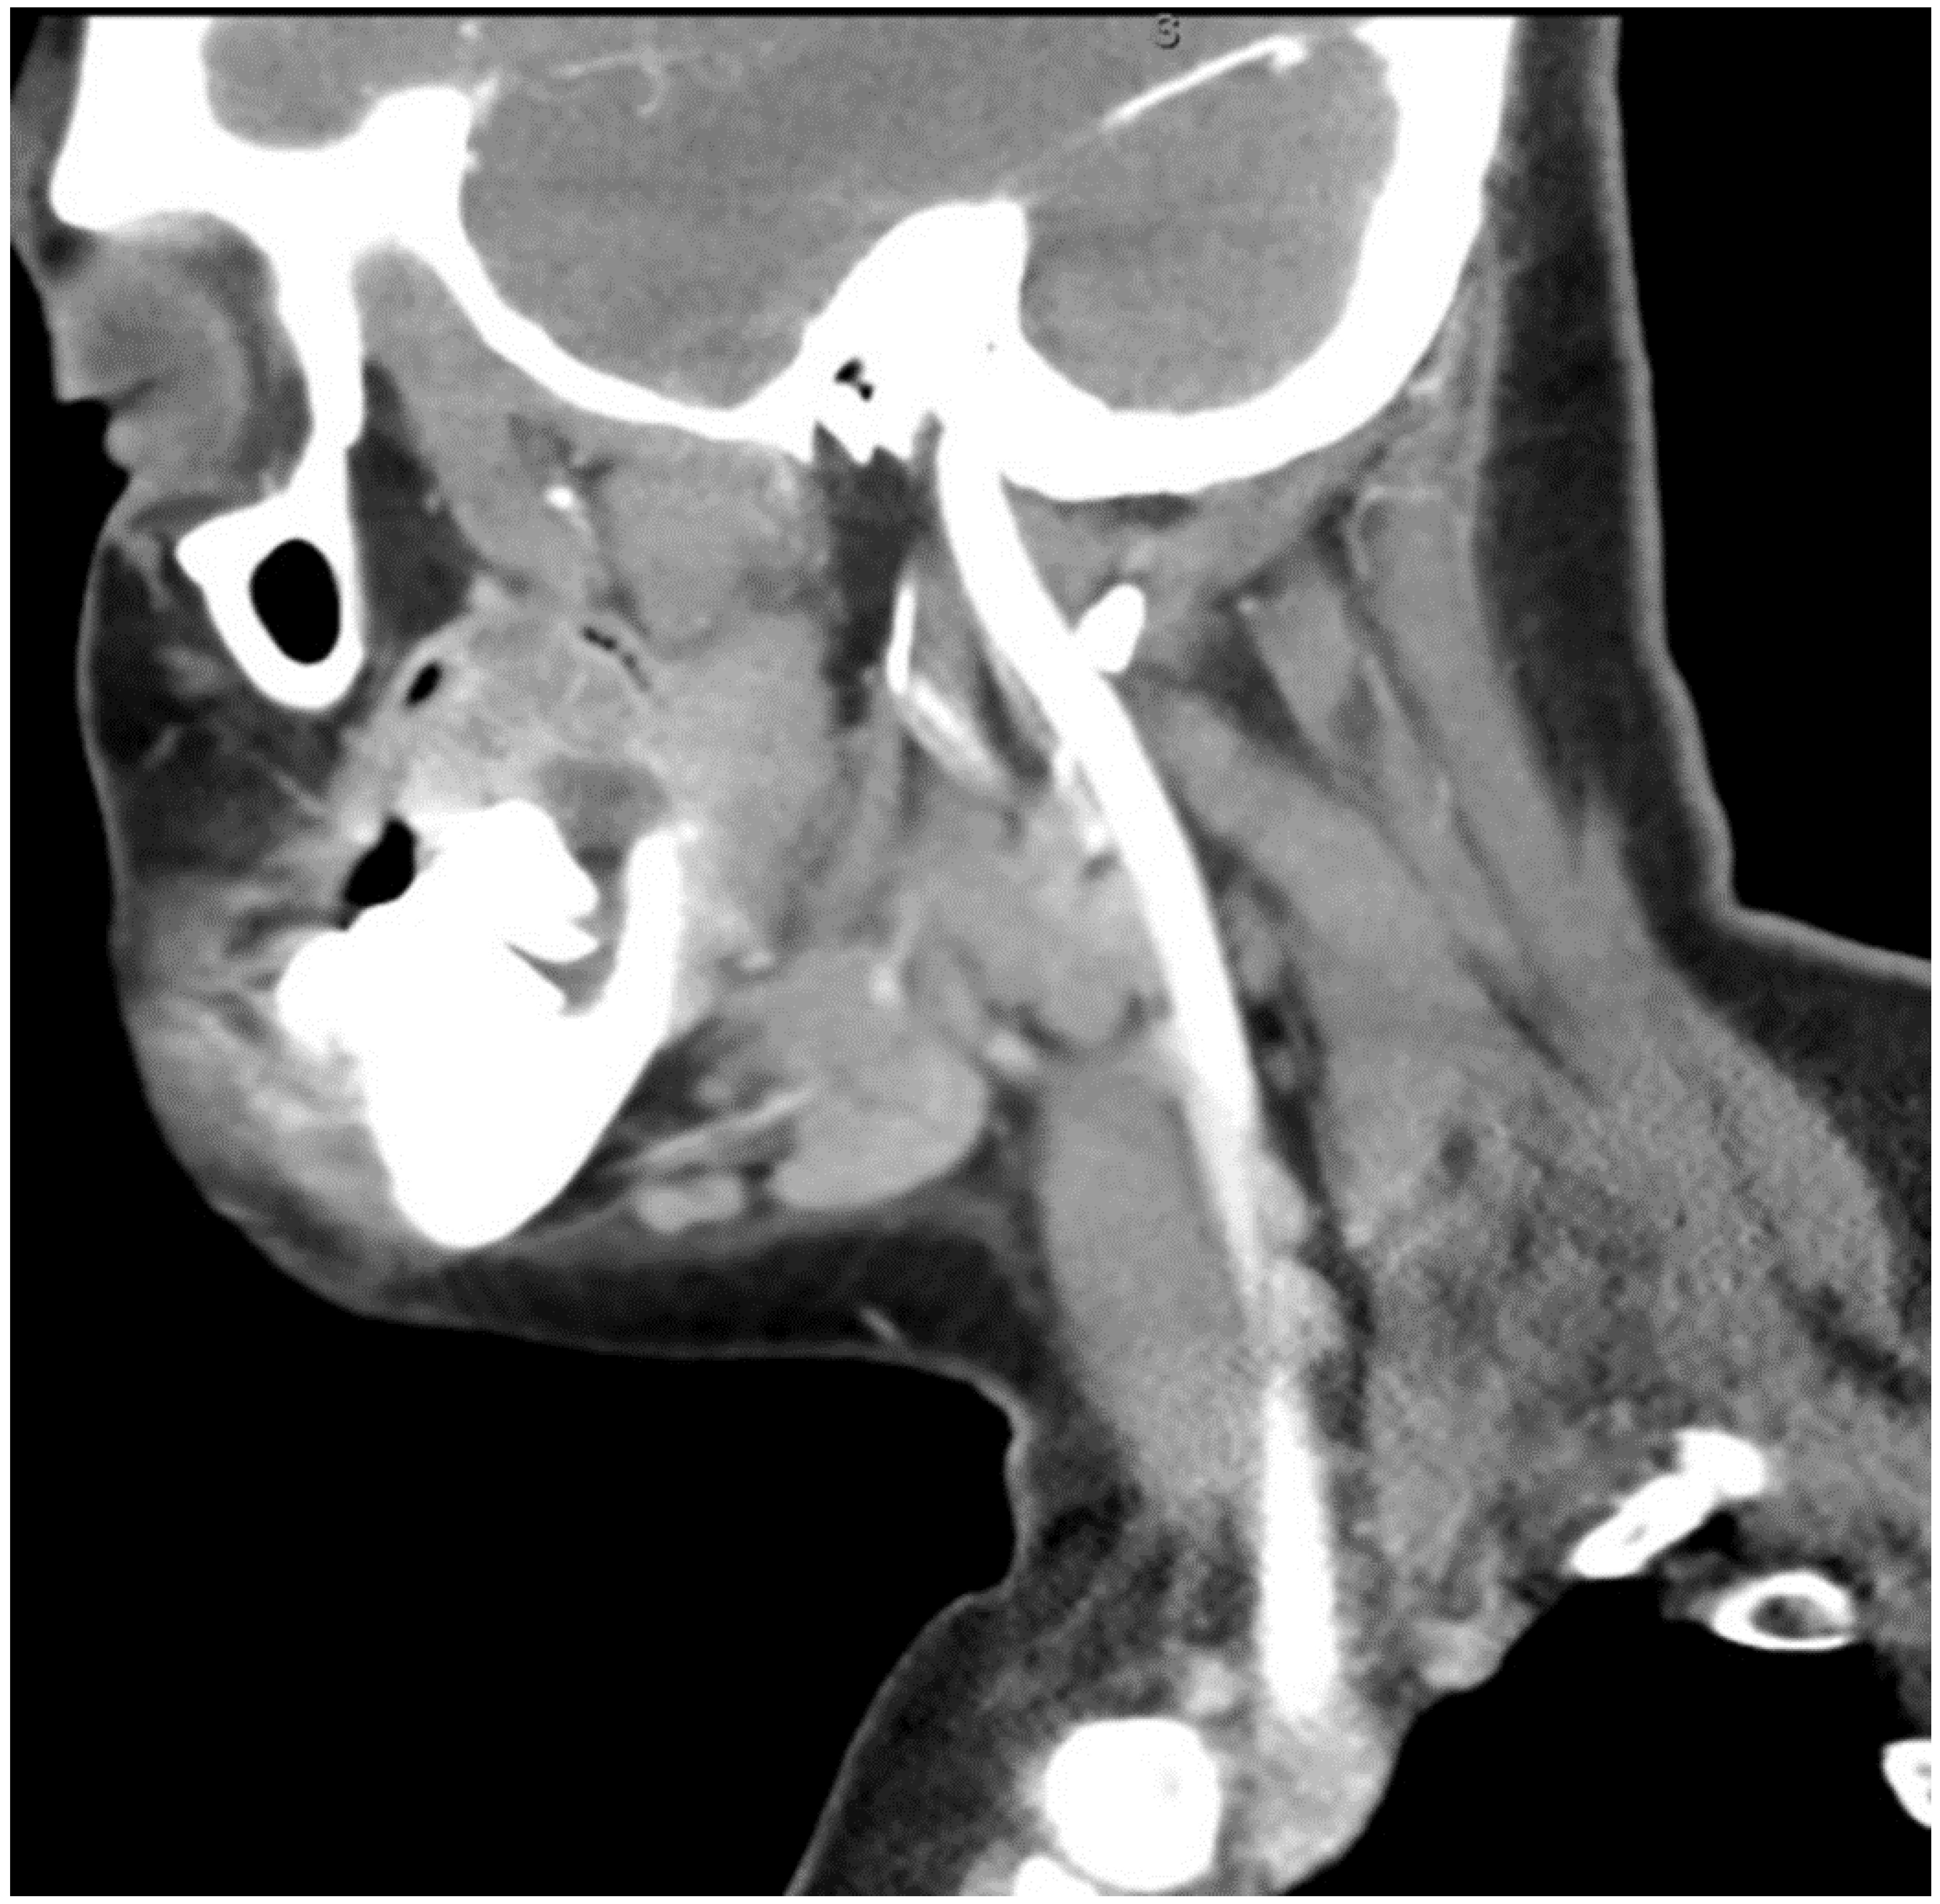

Figure 2.

CT Scan with contrast showing the mass extending to the oropharynx with complete airway obstruction.